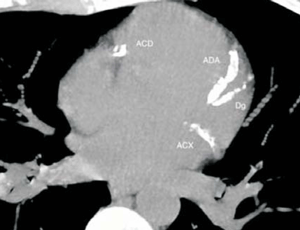

2. Número de vasos involucrados: el modificador N debe incluir cuántos vasos presentan calcio, considerando el tronco de la coronaria izquierda, la arteria descendente anterior, arteria circunfleja y coronaria derecha (n = 1-4) (figura 3).

Figura 3: Se observa calcificación coronaria a nivel de las tres arterias principales. Según el sistema CAC-RADS, se reportaría un score > 300 UA, que compromete la arteria coronaria derecha (ACD), arteria descendente anterior (ADA) y arteria circunfleja (ACX), por lo tanto, CAC- RADS A3/N3.